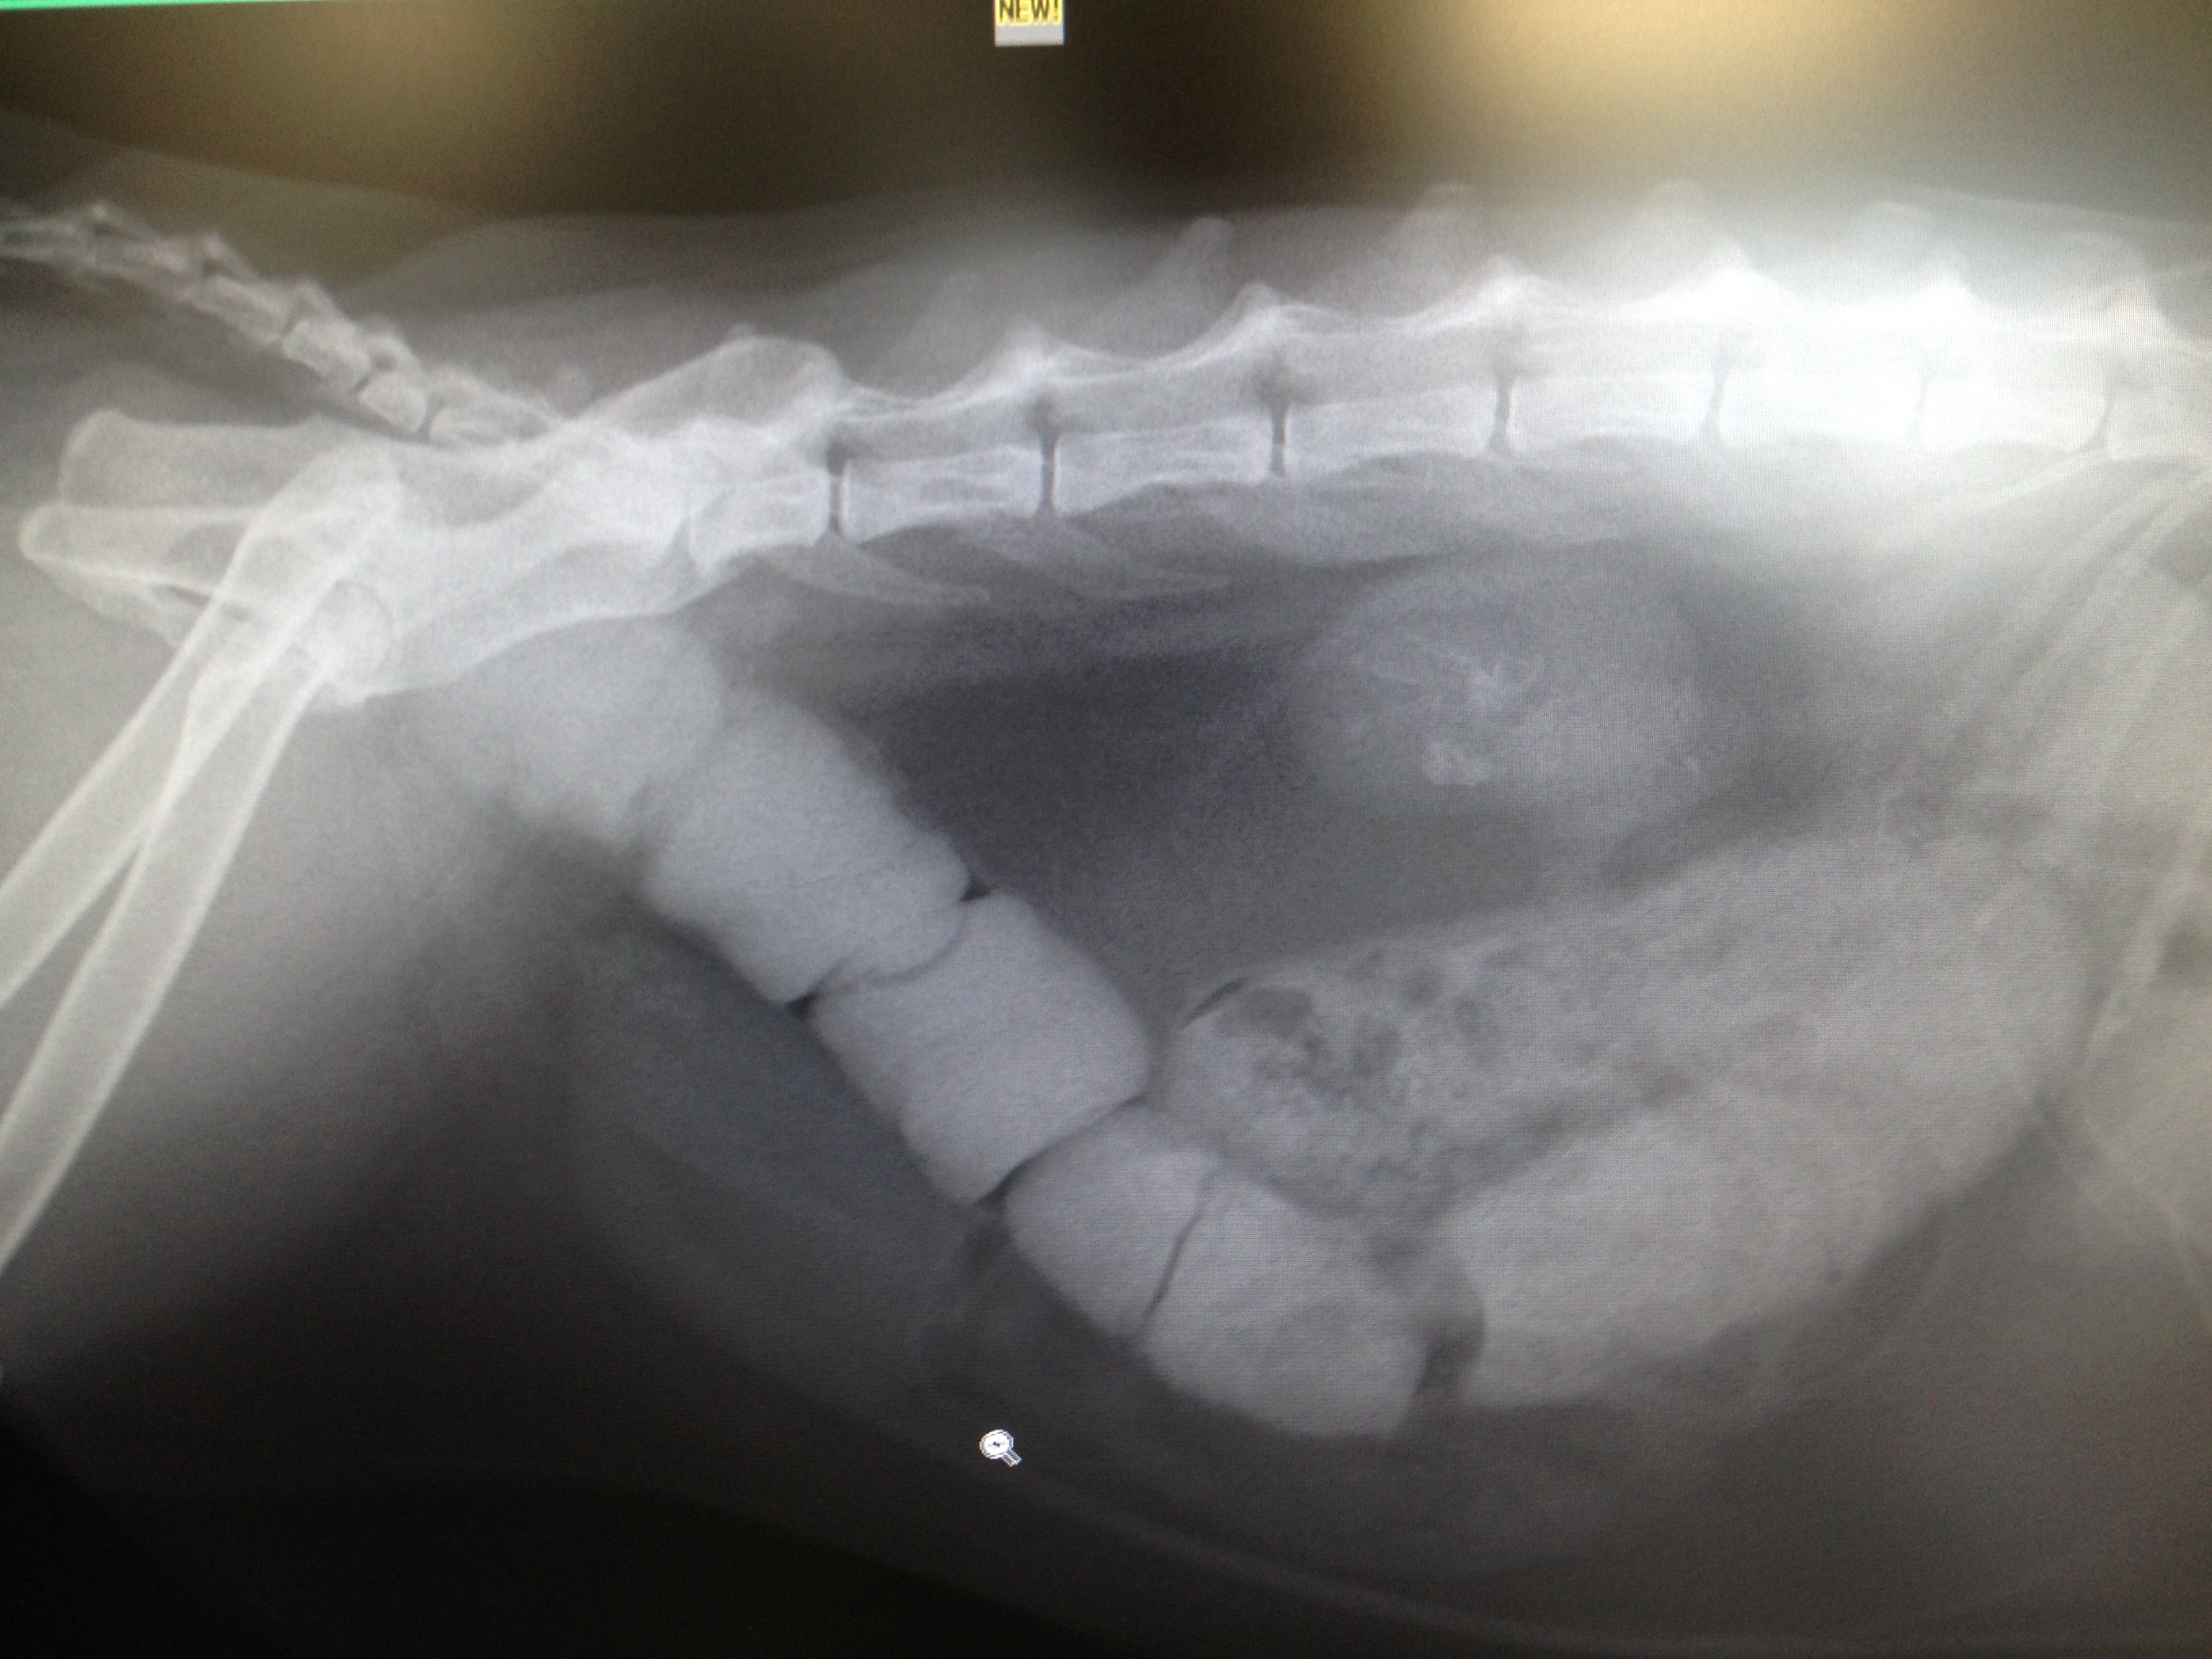

来院時のレントゲン写真 大腸いっぱいに便がつまってます!